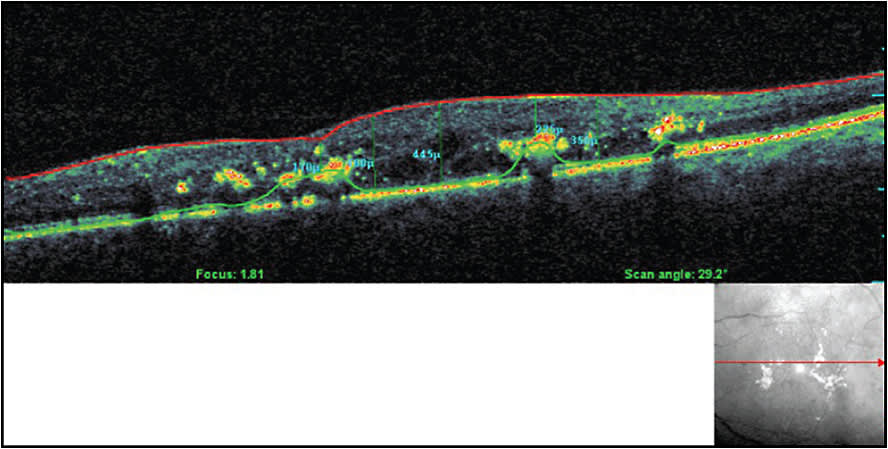

Figure 10. OCT shows cystic central DME.

Figure 11. OCT for the same patient in Figure 10 shows DME resolution after four injections of anti-VEGF and deferred focal micropulse laser.